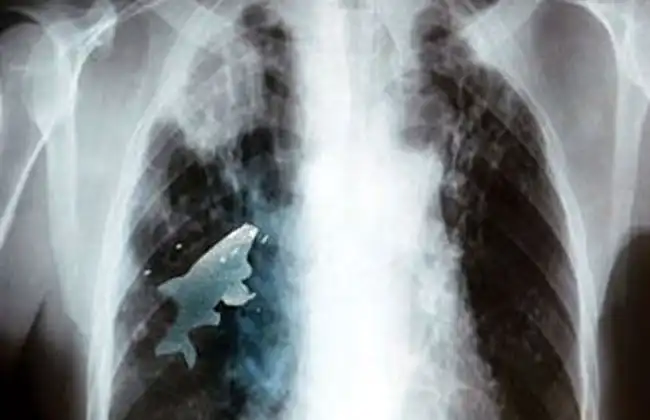

12-летний индийский мальчишка Анил Барела из штата Мадхья-Прадешкак-то проводил время с друзьями на реке. В ходе игр Анил почувствовал, что ему стало очень тяжело дышать, после чего обратился за помощью к врачам. В лёгких мальчика был обнаружен посторонний предмет, а в ходе операции хирурги извлекли из лёгкого почти 9-сантиметровую рыбину.

«Игра» с проглатыванием живой рыбы достаточно популярна среди местных детей, но Барела, скорее всего, намеренно решил попробовать её «вдохнуть», так как с трудом верится, что такое крупное животное могло попасть в организм Анила случайно.